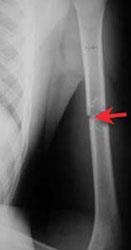

Unlike some other forms of cancer, there are currently no special tests to detect bone cancer before symptoms appear. But it doesn't feel like it. You may learn of your diagnosis after a routine screening or exam, after months or years of coping with undiagnosed symptoms, or even after just feeling like something is off. This is called a cancer of unknown primary. It can spread to distant organs, such as the lungs. A sudden, noticeable new pain is the most common symptom of cancer that has spread to the bone. Cancer in bone can cause intermittent or progressively severe localized bone pain where the cancer is in the bone. Primary bone cancer is a malignant, or cancerous, tumor that originates in a bone.

Kind of like a bruise, but the pain is 'intermittant' and there is no redness, discoloration, or lump. This gradually progresses to a persistent ache or an ache that comes and goes, which continues at night and when resting. When a bone tumor grows, it presses on healthy bone tissue and can destroy it, which causes the following symptoms: Sometimes, people with bone sarcoma do not have any of these changes. In fact, noncancerous bone tumors are much more common than cancerous ones. Bone tumors happen more often in people who've had radiation, stem cell transplants. A cancer cell may break away from the original location in the body and travel in the circulatory system until it gets lodged in a small capillary network in bone tissue. Primary bone cancer is very rare. 3 with metastatic bone cancer, the spine is the most common area affected, and back pain is the most common symptom. Pain is the most common symptom of bone cancer, but not all bone cancers cause pain. At first, the pain is not constant. Pain from bone cancer may be worse at night or when you move the bone. Persistent or unusual pain or swelling in or near a bone can be caused by cancer or by other conditions.

With primary bone cancer, the pain most often occurs in the long bones of the body, like those of the arms and legs. Pain from bone cancer may be worse at night or when you move the bone. It can be hard to tell the difference between bone metastasis pain and pain due to arthritis or an exercise strain. Bone cancer is rare, making up less than 1 percent of all cancers. Cancer may also spread to bone from the adjacent cancer, though this occurs less frequently than spread by the bloodstream. But it doesn't feel like it. Bone marrow is a soft, spongy tissue that is in the center of most bones. This is called a pathological fracture, which means the break in the bone is due to disease and not caused by an accident. Bone pain pain caused by bone cancer usually begins with a feeling of tenderness in the affected bone. Sometimes cancer in bone weakens the bone to such a degree that it leads to breaking of the bone (bone. You may learn of your diagnosis after a routine screening or exam, after months or years of coping with undiagnosed symptoms, or even after just feeling like something is off. Several types of cancer, including multiple myeloma, leukemia, and lymphoma, can develop in the bone marrow. One of the main symptoms of bone cancer is pain in the affected bone.

Persistent bone pain that gets worse over time and continues into the night swelling and redness (inflammation) over a bone, which can make movement difficult if the affected bone is near a joint Sometimes cancer in bone weakens the bone to such a degree that it leads to breaking of the bone (bone. Cancer in bone can cause intermittent or progressively severe localized bone pain where the cancer is in the bone. Although fever is rarely an early sign of bone cancer, it is a sign that the body is fighting an infection or illness. The usual treatment for bone cancer is surgery, and it has a good outlook.